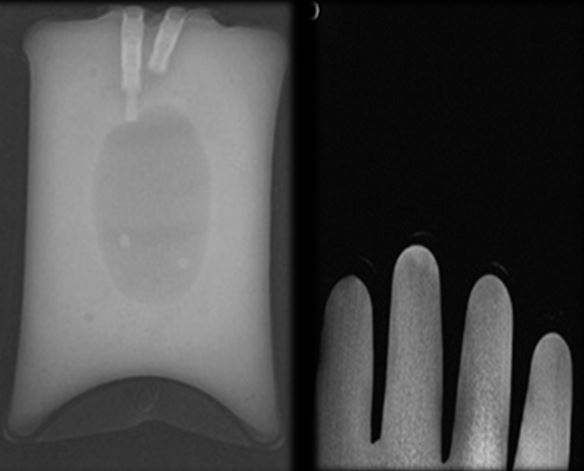

8

Calibration mask

You calibrated the detector with something in the way and so it is on there all the time.

Recalibrate